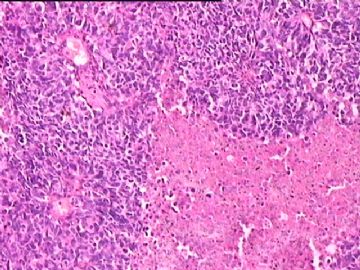

女,34y,头痛一月,右额叶占位:5*5*4cm。囊性区域,4cm。大体:3.5x3x1cm灰白间暗褐色组织一堆,质嫩。临床诊断1:胶质瘤,2:血管母细胞瘤。

本人县级医院头颅手术少,考虑胶质母细胞瘤。大家指导指导。

同意胶质母细胞瘤。细胞异型、坏死、核分裂、血管内皮肿胀增生均可见到。

This is certainly a WHO grade IV malignant neoplasm. While most likely a glioblastoma, I would carefully rule out PNET by staining for GFAP and neuronal markers such as synaptophysin, NeuN and NSE. Rarely, PNET may shows marked pleomorphism and indistinguishable from glioblastoma on HE stain.

同意马老师的意见,该肿瘤从形态及年龄来看考虑PNET或GBM,须标记Syn、NSE、S-100、NeuN和GFAP来鉴别。

结合图片细胞形态特点考虑胶质母细胞瘤,组化标记排除其他